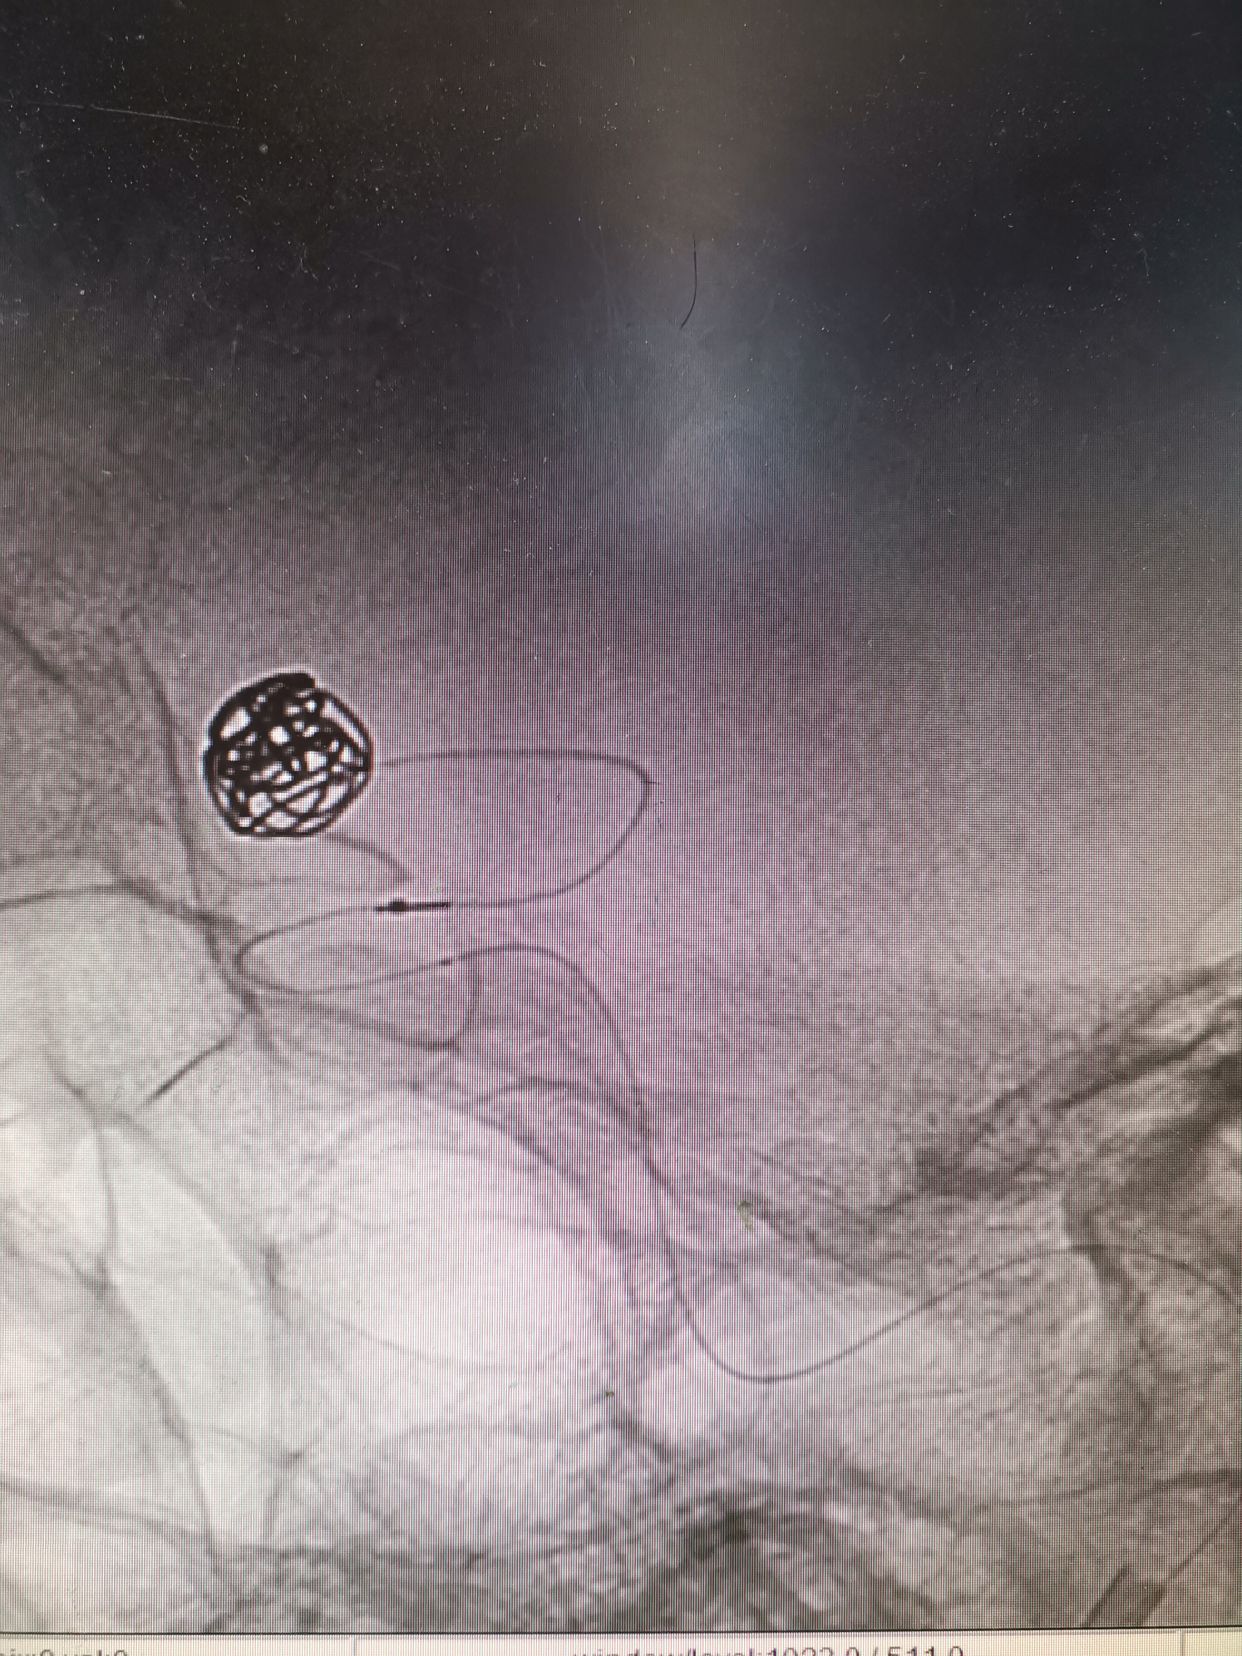

微导管到位后,填入Cosmos Complex 7mm/22cm

继续填入Complex 6mm/26cm

继续填入Complex 6mm/18cm

继续填入Complex 5mm/15cm

术后动脉瘤不显影,双侧大脑前显影。右侧略差。